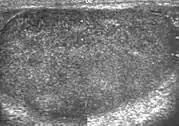

Patients with testicular lymphoma are usually old aged around 60 years of age, present with painless testicular enlargement and less commonly with other systemic symptoms such as weight loss, anorexia, fever and weakness. Bilateral testicle involvements are common and occur in 8.5% to 18% of cases. At sonography, most lymphomas are homogeneous and diffusely replace the testis [Fig. 7]. However focal hypoechoic lesions can occur, hemorrhage and necrosis are rare. At times, the sonographic appearance of lymphoma is indistinguishable from that of the germ cell tumors [Fig. 8], then the patient's age at presentation, symptoms, and medical history, as well as multiplicity and bilaterality of the lesions, are all important factors in making the appropriate diagnosis.

Fig. 9. Leukemia. Diffuse hypoechoic infiltrative lesions are seen involving the whole testis, indistinguishable from that of the lymphoma.